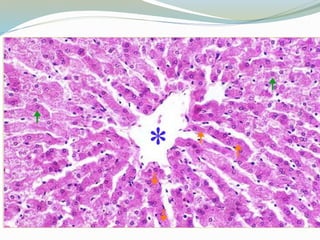

Glándulas salivales principales

 Glándula parótida

 Glándula submaxila

 Glándula sublingual